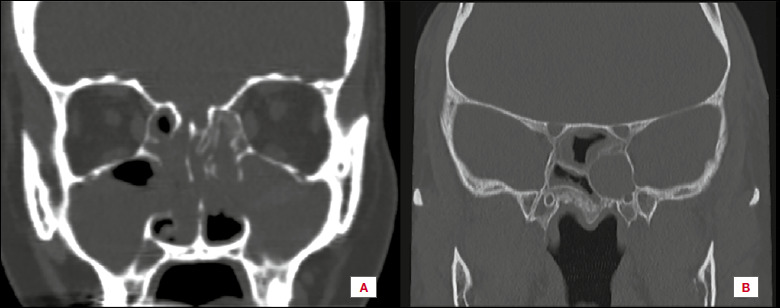

Should computed tomography be used in the evaluation of biologic therapies for severe chronic rhinosinusitis with nasal polyps?